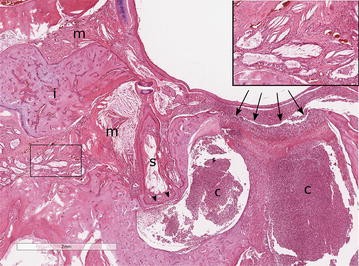

Animals | Free Full-Text | The Formation and Invariance of ...